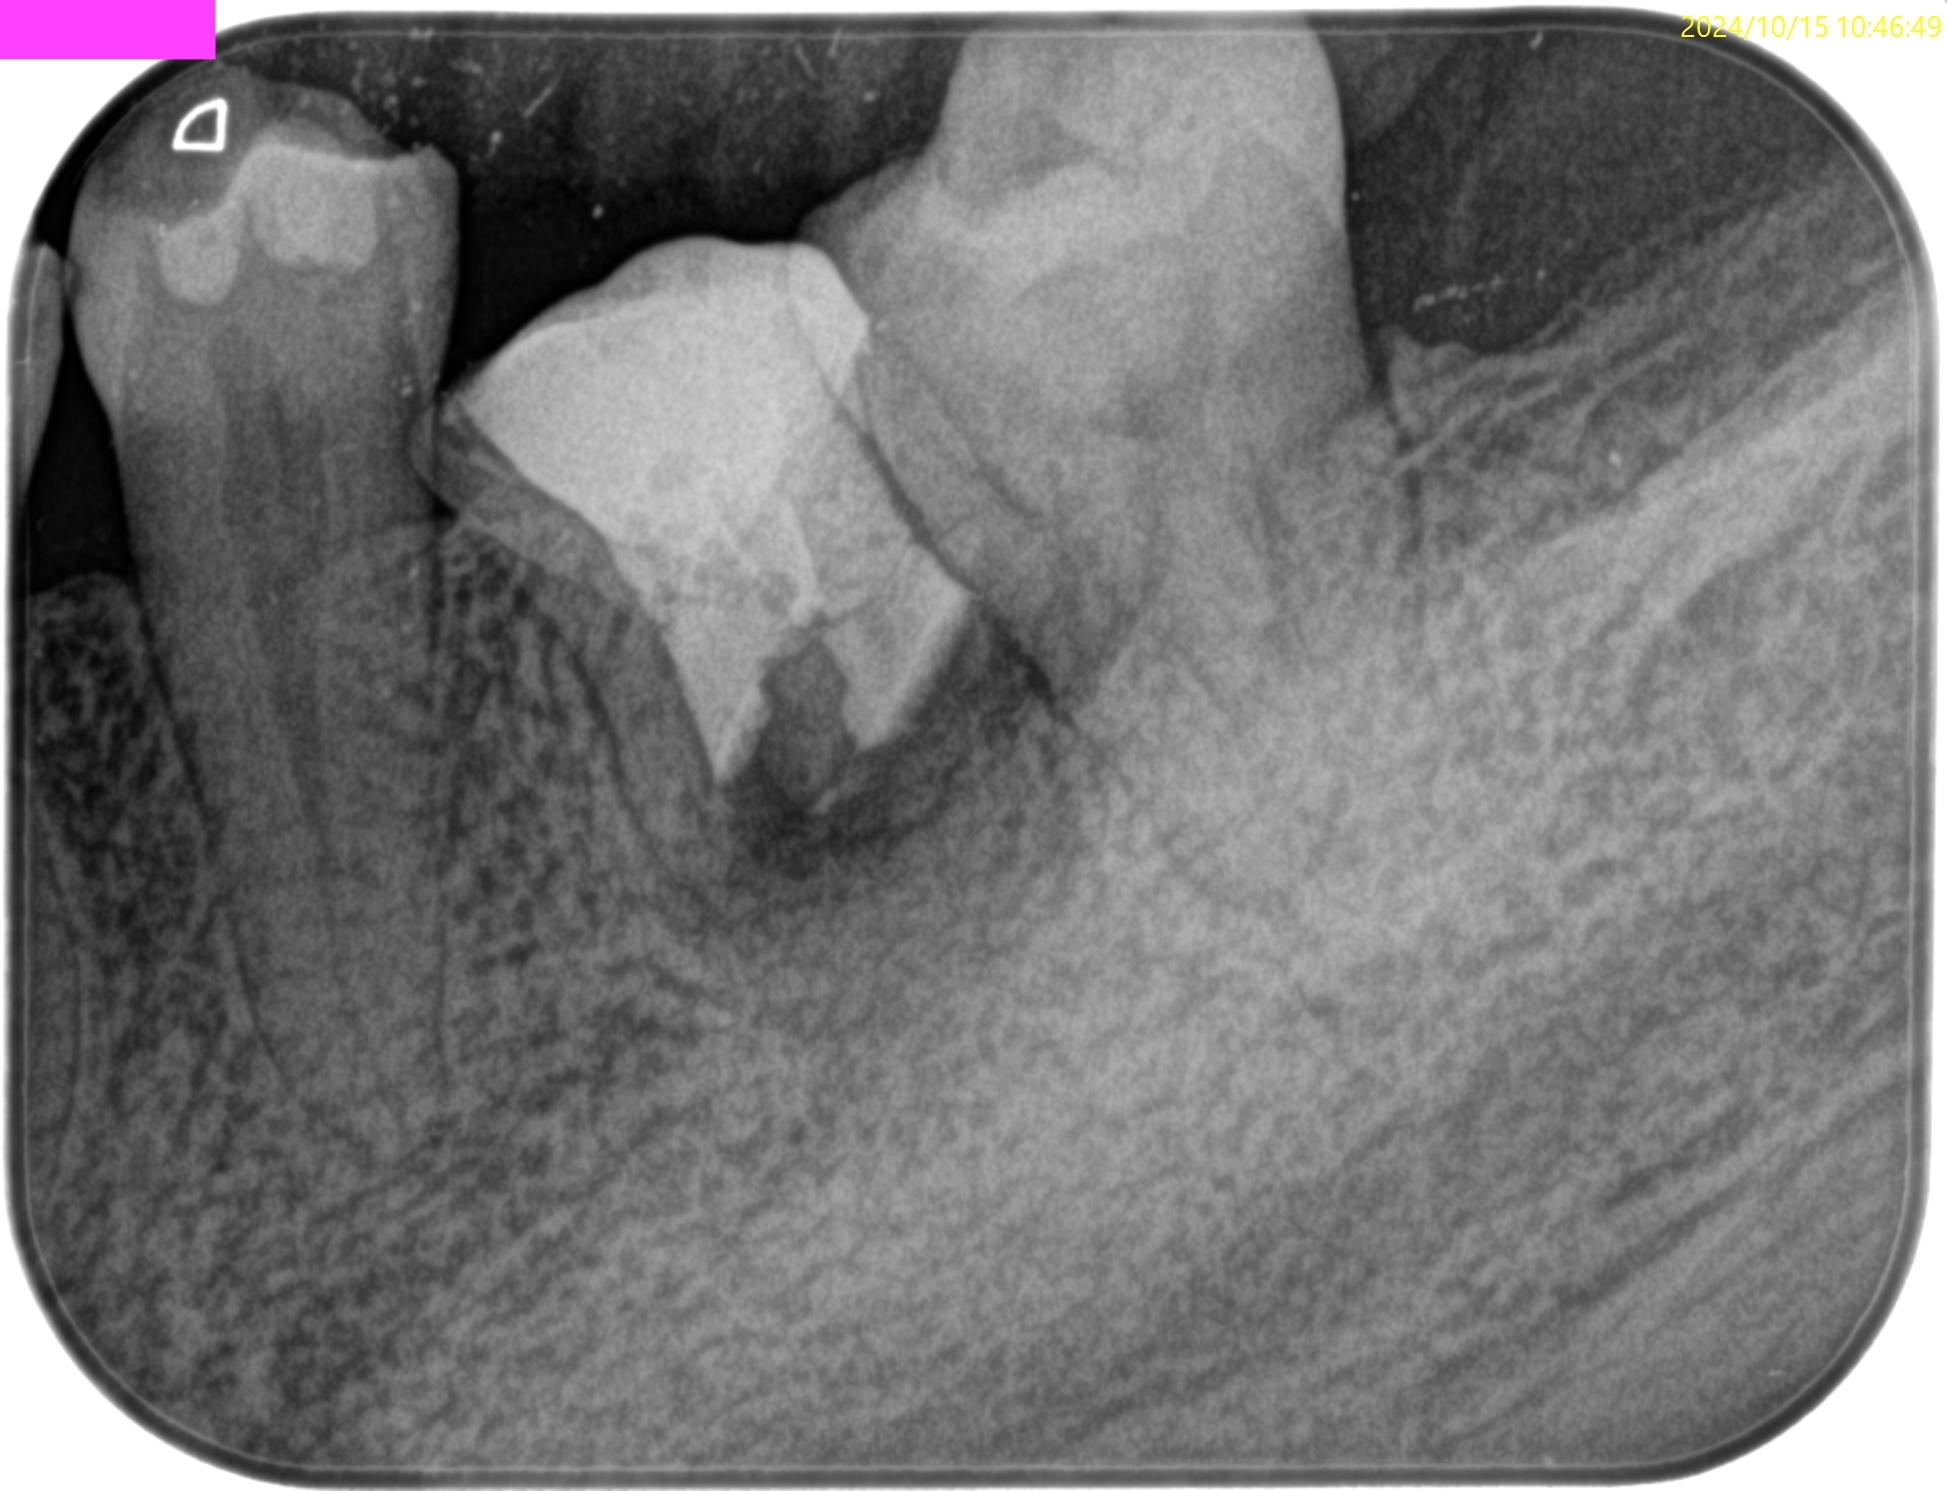

PA(2024.9.12)

CBCT(2024.9.12)